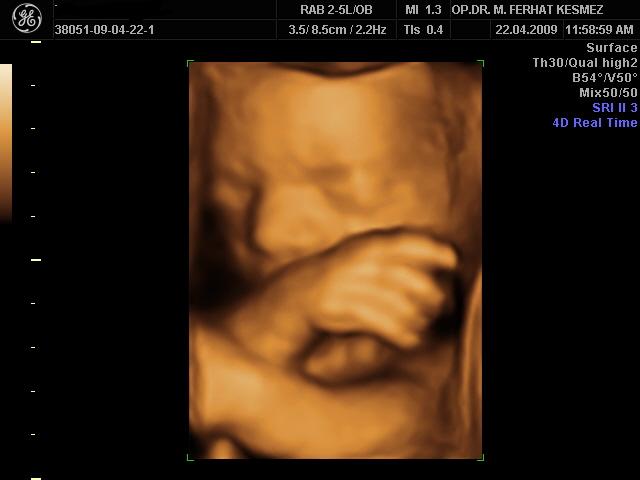

4 Boyutlu Ultrason